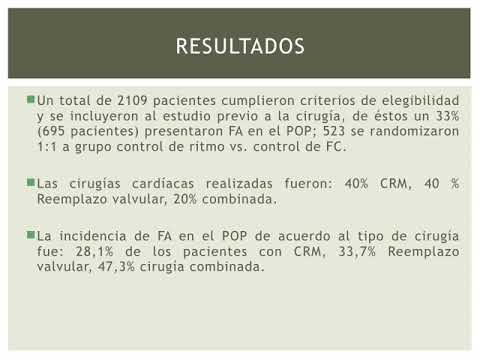

Control de ritmo vs control de FC en cirugia cardíaca. Dra. Florencia Anzivino. Residencia de Cardiología. Hospital C. Argerich. Buenos Aires